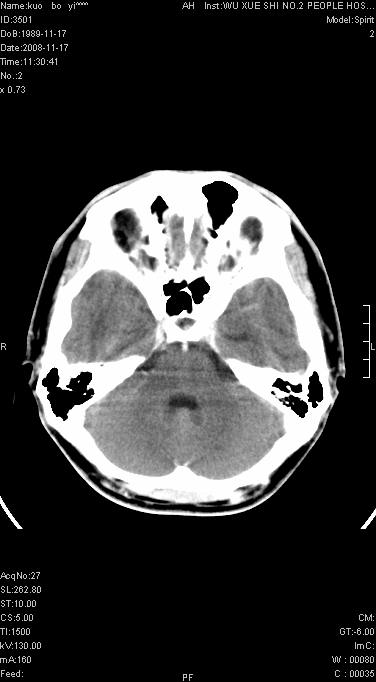

增强已传.年龄19岁.请会诊

增强后水肿中心高密度灶有明显强化,强化不均匀,呈雪花状或絮状,且强化明显,若为肿瘤,应该出现形态较规则的瘤体影,强也有例外如胶质瘤就可以形态不规则.但胶质瘤明显强化者多为恶性间变性,与病史及相关表现太不相符.因此本例多考虑为炎症引起.

本例与重庆中华放射学年会读片大赛上第12个病例(由山东医影研究所柳澄教授提供)有异曲同工之妙(影像表现几乎相同).那个病例我的第一选择是炎症,其次是血管畸形,最后选项择的占位.但得到的答案是ms,新发的ms灶可见明显强化,但这么大的病灶着实没有想到,可能本例就影像表现来说也不能排除ms可能

患者年龄才19岁,病史很短,也较符合炎症等短程病变.

左顶叶较大范围水肿区,内见明显强化的片状 棉絮状组织,但占位效应不明显。多考虑:脑炎!

支持脑炎\\脑脓肿(早期).

给我的整体感觉 以脑炎性病变可能大,结合实验室检查以除外结核性病变

还是考虑原发脑胶质瘤,梗塞缺血水肿的低密度要同时累及皮、髓质并要符合动脉供血的区域分界特点,本例强化后见瘤体结节及向周围浸润生长的瘤血管都强化了,水肿广泛呈指状,占位效应使同侧脑皮质受压变薄、脑沟消失但因实质性的瘤体尚小所以中线无明显移位。不知各位同意这样分析吗?(转移瘤多为多处病灶)

首先考虑脑胶质瘤。有明显的左顶叶脑白质水肿,病变轻度占位效应,花环样强化,脑炎——影像不支持!

左顶叶大范围水肿,内见明显强化的片状 棉絮状组织,但占位效应不明显。考虑脑炎可能性大。

在北京天坛医院治疗考虑寄生虫感.明显好转